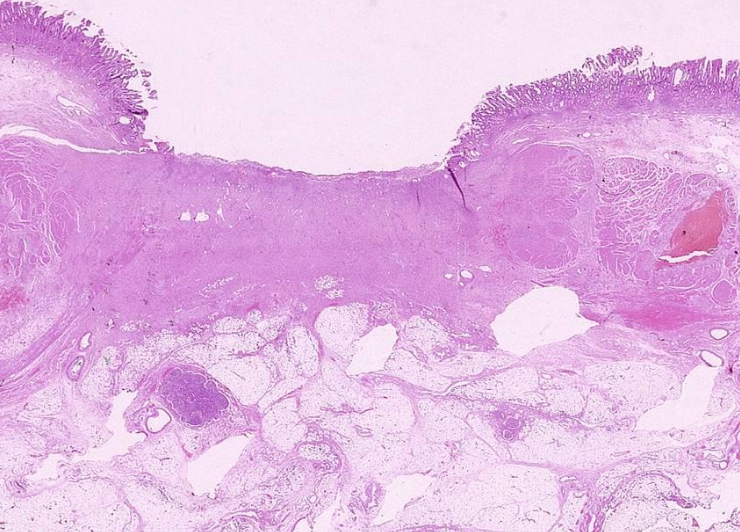

A

Ulcer

Crohn’s Disease with full thickness edema and inflammation